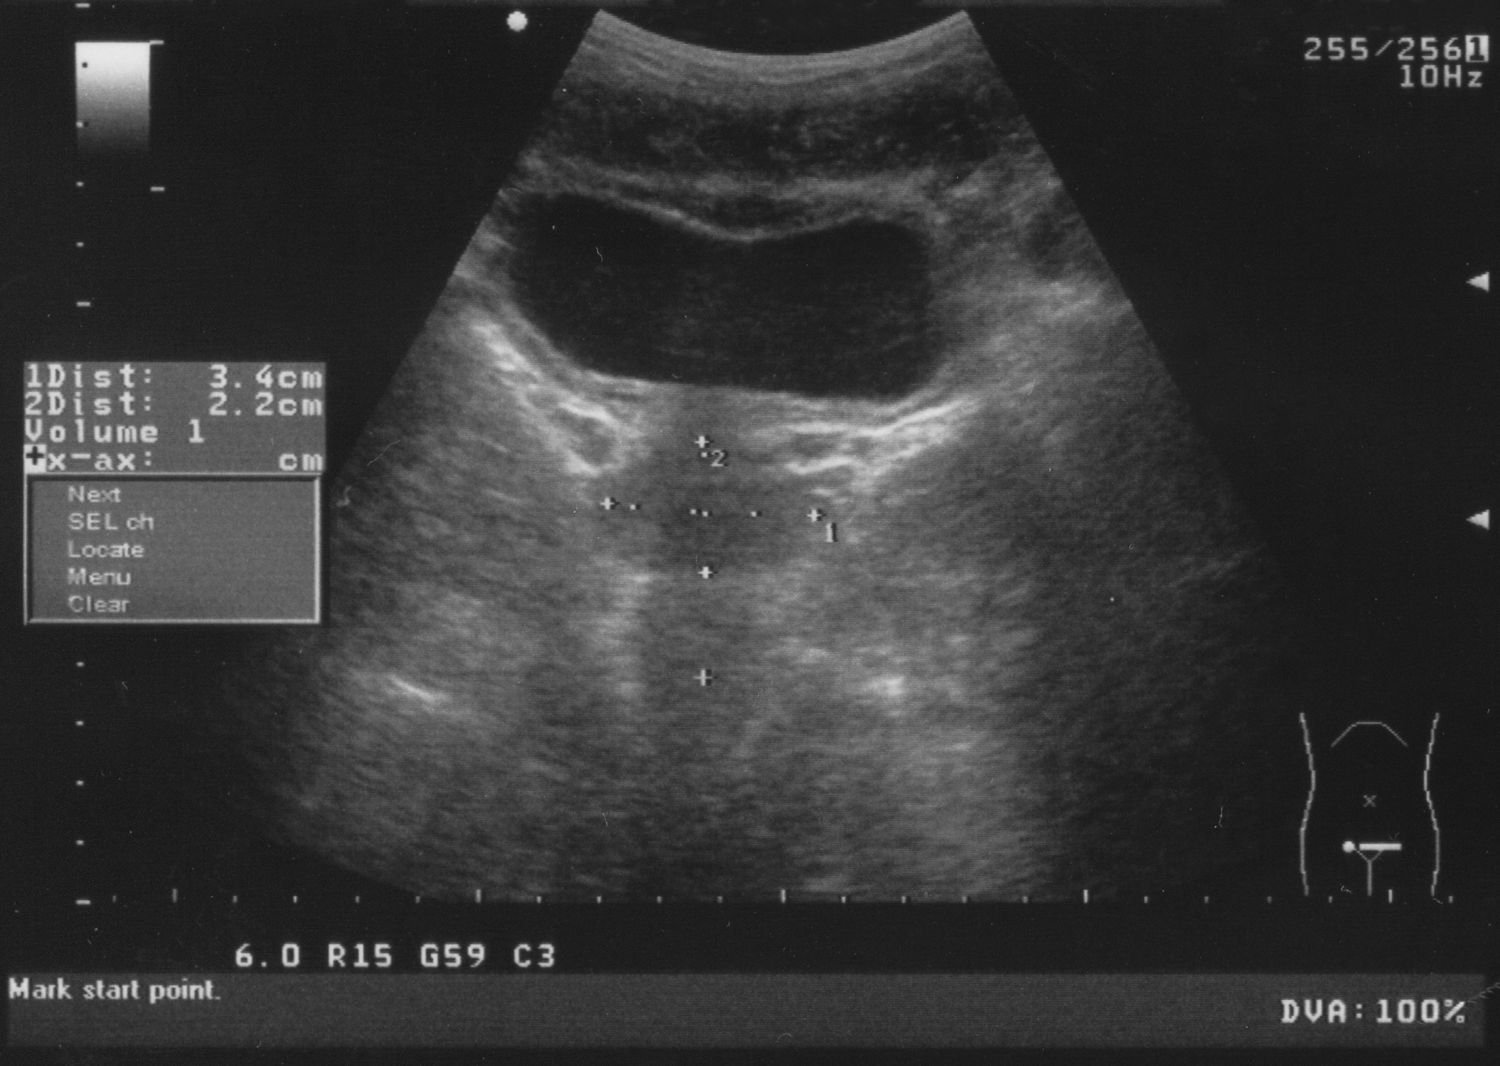

Ultrasound & Urine Analysis

Early detection of kidney stones, infections, and blockages using advanced imaging.